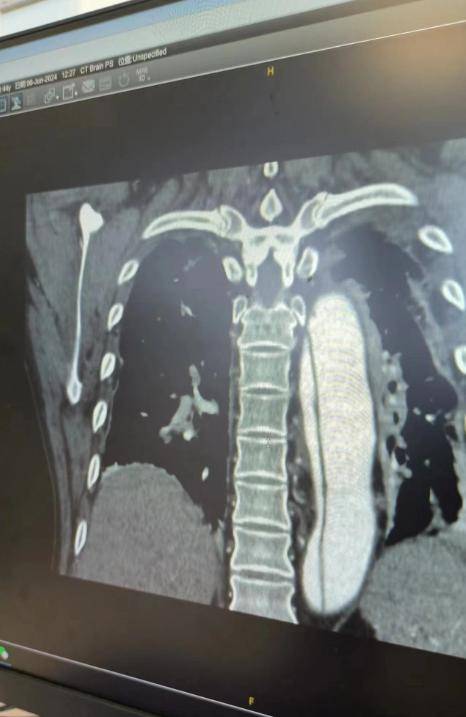

4月13日凌晨,麥友煊在汕尾某街道吃宵夜,吃到一半突然倒地不起,後來緊急上了救護車被送往醫院,並被診斷出是腦出血。

麥友煊住院十幾天才度過危險期,雖然恢復了意識,但是依舊神志不清,生活不能自理,之後他的家人將其轉到深圳接受救治,卻在6月15日,被下達了病危通知書。